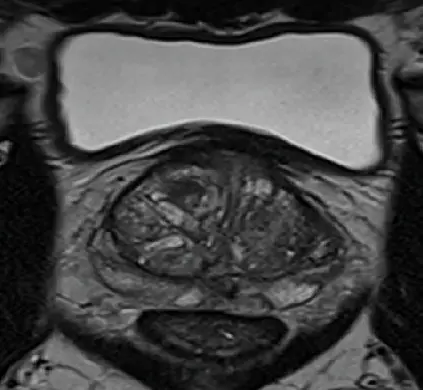

Prostatavergrößerung

T2w coronal

Die Untersuchung umfasst verschiedene Bildsequenzen (=multiparametrisch), darunter:

• hochauflösende T2w- Aufnahmen (Beurteilung der Anatomie)

Diese Kombination ermöglicht eine sehr genaue Beurteilung nach international anerkannten Kriterien (PIRADS-Befundungsschema).